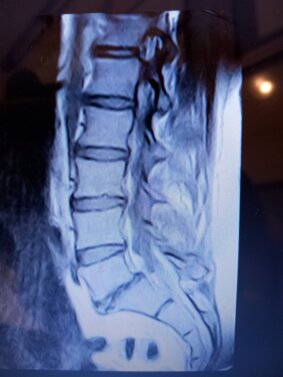

SCHIENA: Rachide lombare

trattamento con fisioterapia della lombosciatalgia,

lombalgia,

sciatalgia,

falsa sciatica,

listesi vertebrali

cedimenti del corpo vertebrale